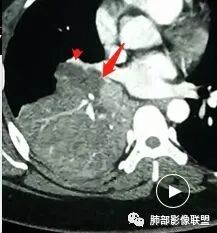

关键点——中间段支气管堵塞处

通过视频显示中间段堵了

支气管腔内占位

远端低强化,提示粘液很多

本病例特点是中叶病灶和下叶病灶不一样,支气管腔内的病灶又是怎么样的呢?我们要是有沿支气管重建的冠状位、矢状位会更有利于分析。第一,中叶病灶明显粘液样改变、低密度,且低密度区有占位效应、膨隆,确实要考虑粘液表皮样癌。第二,中叶和下叶支气管显示不出来,但血管显示出来了。中叶病灶血管稀疏、细小,下叶病灶血管粗大、走形正常。朝外肺不张实变,不是单纯的肺不张,肺不张一般体积明显缩小、血管聚拢,该病例肿瘤于其中成分不一样,所以上叶部分病灶考虑为下叶病灶占位效应及膈面向上推压引起,中叶萎缩。综合腔内堵塞、纵隔淋巴结肿大要考虑恶性。

支气管层面位置朝下强化明显,支气管腔内、远端是有差异的,腔内哪些是粘液?哪些是肺组织?是单纯实变?还是合并感染?还是外围都是病变?支气管腔内病变?

3.中间段支气管阻塞,腔内隐约见息肉样结节或突入,结节有较明显强化,这很重要,说明它有生命力,强烈提示新生物,而非分泌物或异物等等。

可惜腔内腔外混沌一片,我们不能分辨管壁及管壁外细节,我们不能判断新生物实际大小,不能判断局部支气管彻底破坏还是结节影跨越腔内外。

4.年轻、女性,支气管腔内相关新生物,会想到类癌或涎腺类肿瘤,如粘液表皮样癌等。强化较明显类癌可能性较大。支气管鳞癌和间叶组织肿瘤的可能性都非常小。